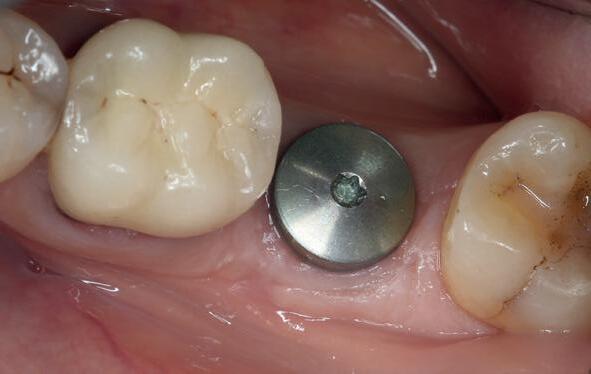

Afbeelding 1 en 2. Een immediate placement (afbeelding 1) is maar weinig invasief en zal weinig nalast geven. Bij een uitgebreide botopbouw (afbeelding 2) daarentegen is de wond veel groter en kan er meer nalast verwacht worden.

Er wordt besloten om botmateriaal te plaatsen in de extractie-alveole. Vervolgens wordt het afgesloten met een titanium versterkt d-PTFE membraan (afbeelding 2). Na vier weken wordt het membraan verwijderd.

Zes maanden na extractie wordt het implantaat 37 geplaatst. Er is sprake van een goede genezing en de processushoogte en -breedte zijn behouden en opgebouwd. Ook is er zichtbaar gekeratiniseerd weefsel

gewonnen. De wond kan na het plaatsen van een healing abutment primair gesloten worden (Afbeelding 3a-3d).

In afbeeldingen 4a-c is het resultaat drie maanden na het plaatsen van het implantaat te zien. De genezing is volledig en de verwijzer kan de suprastructuur vervaardigen (afbeelding 4a-4c).

In afbeeldingen 5a-d is de implantaatkroon 37 te zien, twee jaar na plaatsing. Op de röntgenfoto is herstel van zowel corticaal als spongieus bot te zien. (De CB-CT was vervaardigd in verband met implantologische indicatie in het naastliggende gebied).